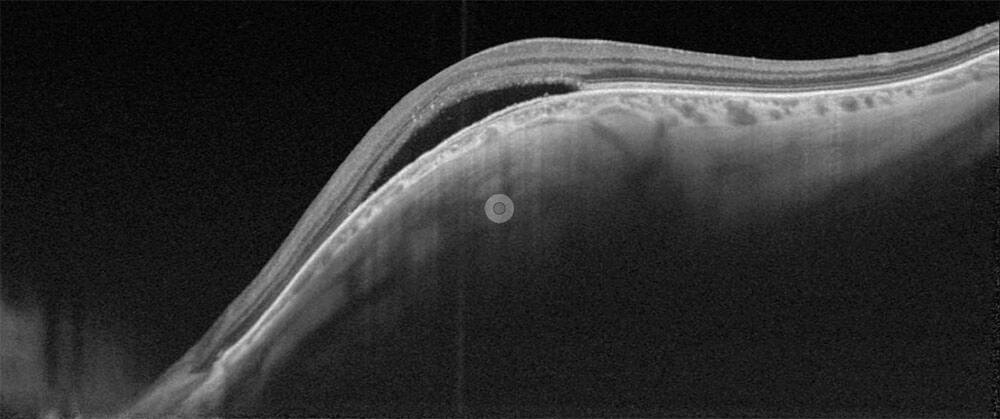

Figure 1. (A) Néovaisseau choroïdien myopique accompagné de fluide sous-rétinien.

(B) OCT B-scan horizontale identifiant du fluide sous-rétinien. Il existe une lésion hyperréflective à bords flous avec une hyporéflectivité postérieure et l’absence d’effraction de l’épithélium pigmentaire. (C) La diffusion tardive à l’angiographie à la fluorescéine confirme le diagnostic.